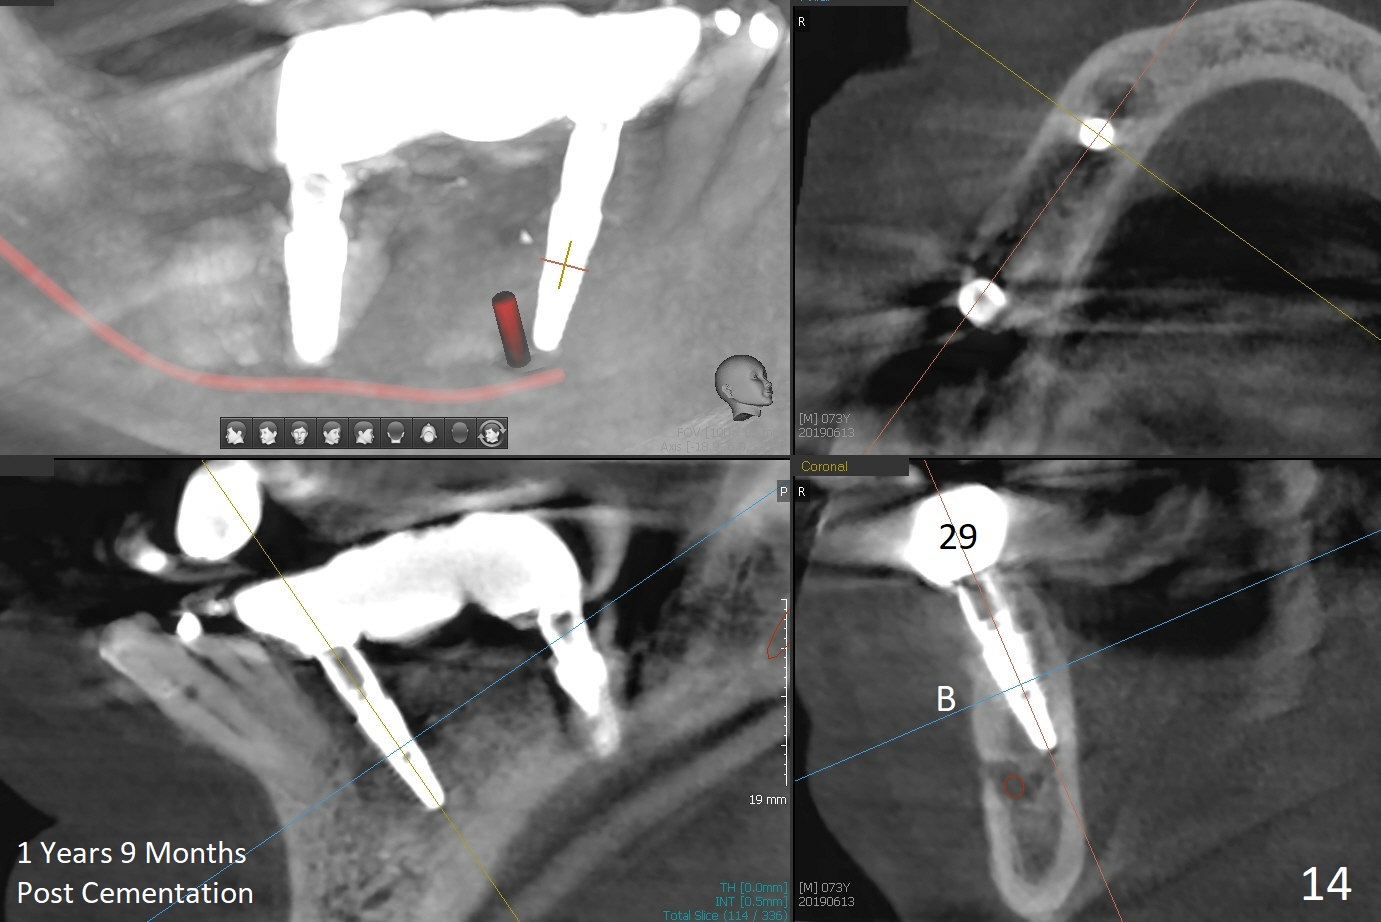

The patient will return in two weeks (total 2 months postop). The abutment at #29 will be changed to a longer one (3.9x7(6) mm). Provisional FPD will be fabricated with an emphasis to push the surrounding (especially lingual) gingiva away from the abutments, most likely using gauze as gingival retraction cord. The crown at #2 will be trimmed to have clearance. Fig.13 is taken 3 months post cementation. CBCT taken 1 year 9 months post cementation shows the uneven buccal (B) and lingual crests (Fig.14,15 arrowheads).